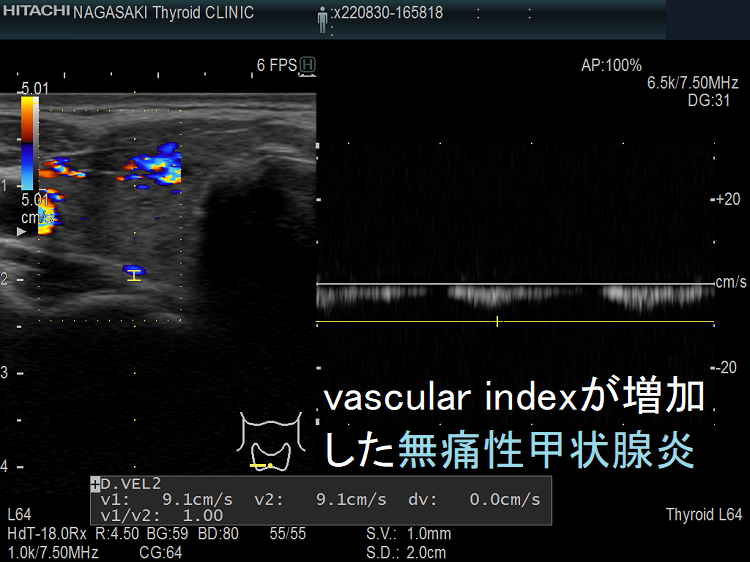

vascular index(血流指数)が増加した無痛性甲状腺炎

vascular index(血流指数)が増加した急性期の無痛性甲状腺炎の下甲状腺動脈の収縮期最大血流速度(ITA-PSV);ITA-PSVは低下しています。

筆者らが、バセドウ病再発・抗甲状腺薬の効き易さ予測目的で開発した下甲状腺動脈の収縮期最大血流速度(ITA-PSV)測定 は、無痛性甲状腺炎と甲状腺機能亢進症/バセドウ病と鑑別するのにも有用です。

無痛性甲状腺炎急性期の下甲状腺動脈収縮期最大血流速度(ITA-PSV)は、正常~低値です。甲状腺機能亢進症/バセドウ病の下甲状腺動脈収縮期最大血流速度(ITA-PSV)は正常~異常高値です。

筆者らが提唱した下甲状腺動脈の収縮期最大血流速度(ITA-PSV)を応用した論文がインドから出ています。甲状腺機能亢進症/バセドウ病と無痛性甲状腺炎を鑑別できる下甲状腺動脈の収縮期最大血流速度(ITA-PSV)のカットオフ値は、30 cm/s(感度91%、特異度89%)としています[Arch Endocrinol Metab. 2019 Sep 2;63(5):495-500.]。

ただ、筆者の経験ではカットオフ値は32.0 cm/s にした方が感度はあまり変わらず特異度が高くなります。特異度は89%程度なので、ITA-PSV 30.0-45.0 cm/s くらいの無痛性甲状腺炎は珍しくありません。むしろITA-PSVのみでバセドウ病と判断すれば診断を誤る可能性があります。

さすがに、ITA-PSV≧50.0 cm/s なら99%バセドウ病のはずです。しかしながら、長崎甲状腺クリニック(大阪)ではITA-PSV≧64.6 cm/sの無痛性甲状腺炎が見つかりました。